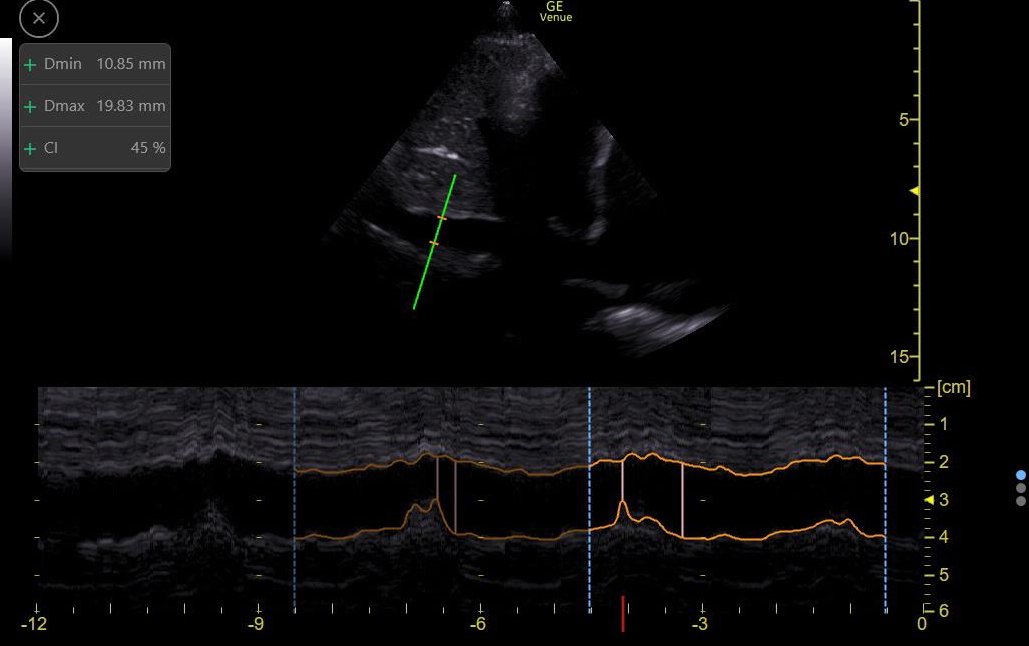

PLAx shows intermittent RV collapse,

It is sometimes hard to tell it this is happening in diastole (a sign of tamponade). So M-Mode through the Mitral Valve can help.

Here it shows clear diastolic collapse!

9/13